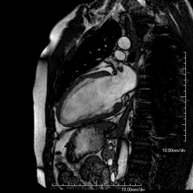

RM Cardíaca

RM CardíacaÉs una prova diagnòstica no invasiva que obté informació morfològica i funcional del cor i les estructures adjacents. D'aquesta manera es poden diagnosticar diferents patologies congènites i adquirides, o bé realitzar controls en pacients amb patologia prèvia ja coneguda. En la gran majoria de casos és necessari l'ús de contrast intravenós (Gadolini) per completar l'estudi, un tipus de contrast que rarament produeix reaccions adverses. Durant la prova el tècnic li demanarà diverses vegades que aguanti la respiració durant 10-15 segons per obtenir les imatges tant clares sigui possible. No es necessita preparació prèvia per part del pacient. La durada de la prova és de 45 – 60 aproximadament. Està contraindicada en pacients amb marcapassos. El pacient haurà d'avisar en cas que porti implants metàl·lics i/o clips quirúrgics.